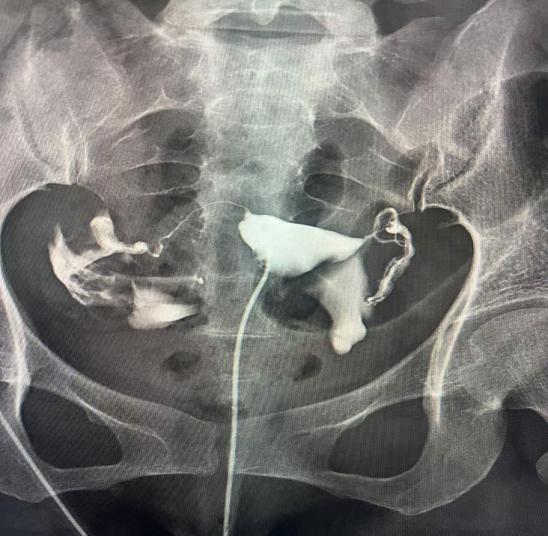

子宮輸卵管造影是通過導(dǎo)管經(jīng)陰道、子宮頸向?qū)m腔及輸卵管內(nèi)注入造影劑,利用X線診斷儀透視并拍片,根據(jù)造影劑在子宮、輸卵管及盆腔內(nèi)的顯影情況,來了解和判斷子宮腔形態(tài),是否畸形、粘連,輸卵管是否通暢,以及輸卵管阻塞的部位。常用于不孕癥、輸卵管再通、子宮畸形等疾病的診治。如